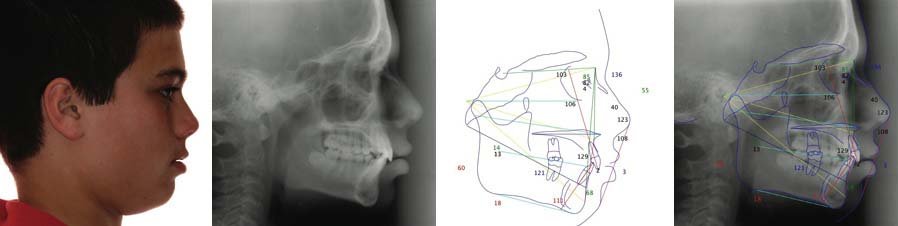

Cas 2 : Hyperdivergence (Face Longue)

Données céphalométriques :

- FMA : 38° (très augmenté)

- Axe Y : 67° (augmenté)

- Axe facial : 84° (diminué)

- ANB : 4° (légère classe II)

- i/m : 95° (trop élevé pour le type facial)

- Hauteur faciale antérieure augmentée

Diagnostic : Hyperdivergence avec rotation postérieure mandibulaire, risque de béance antérieure.

Planification thérapeutique :

- Contrôle strict de la dimension verticale

- Éviter les élastiques verticaux

- Verticaliser les incisives inférieures (réduire i/m)

- Possibilité de mini-vis d’ancrage pour intrusion molaire

- Envisager la chirurgie orthognathique si sévère à l’âge adulte